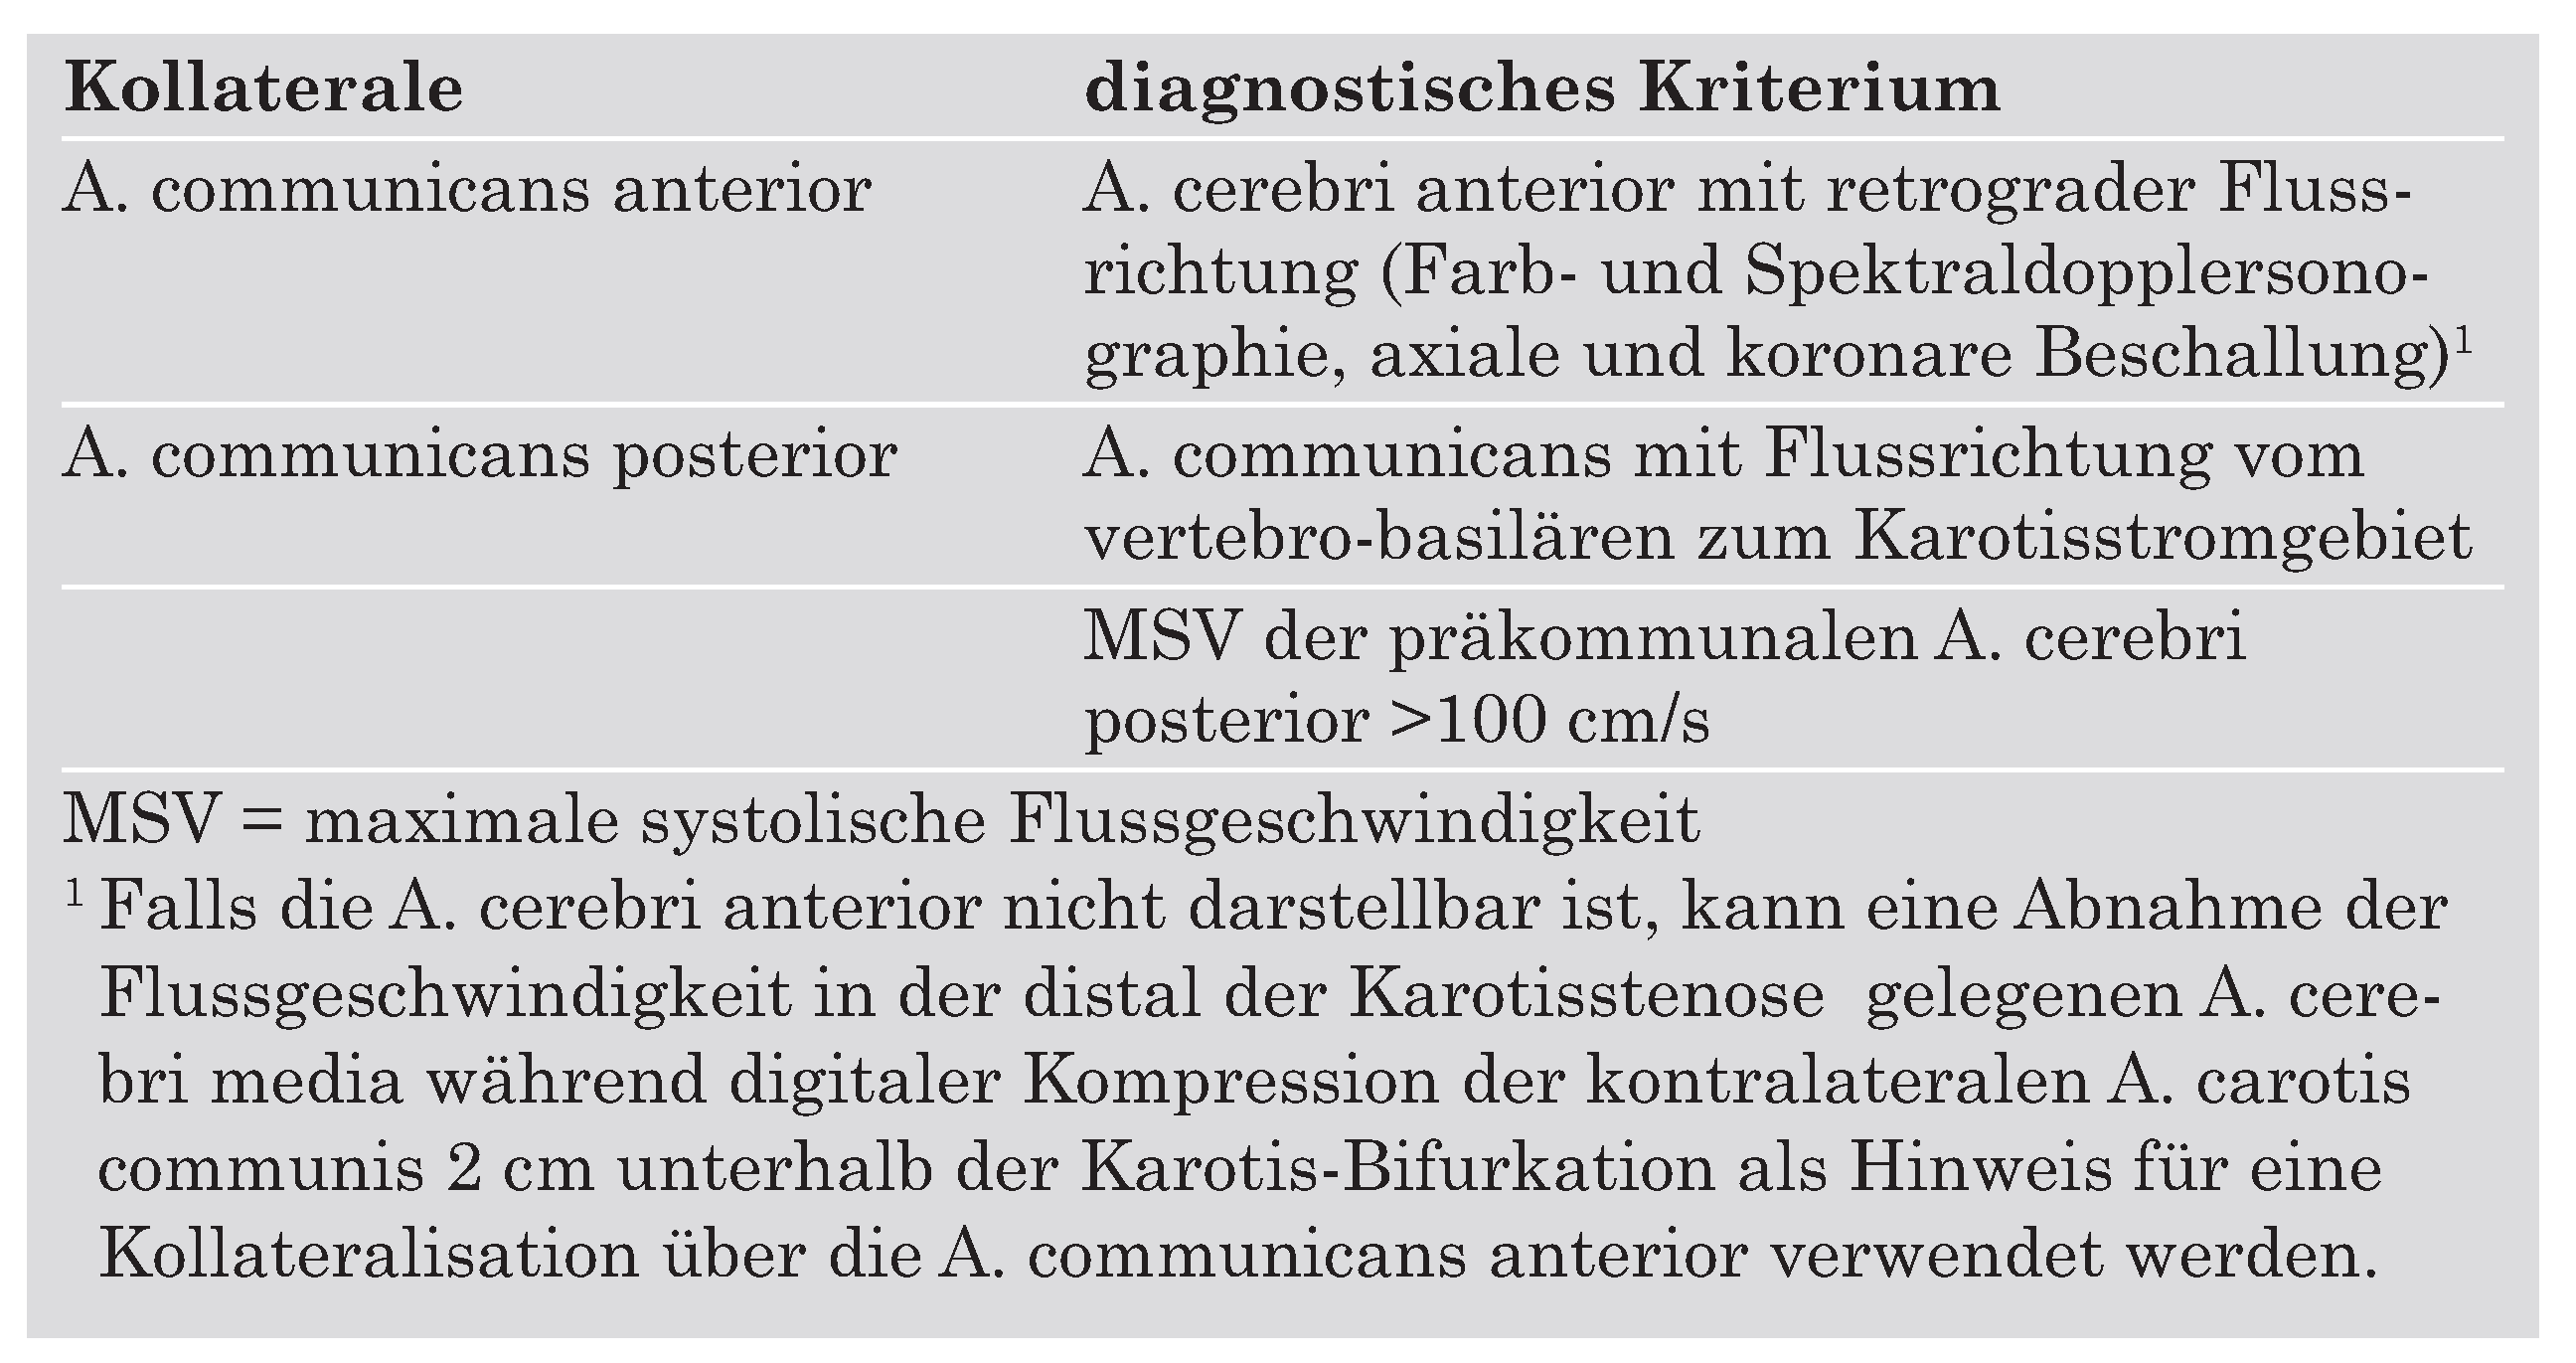

|

|

|